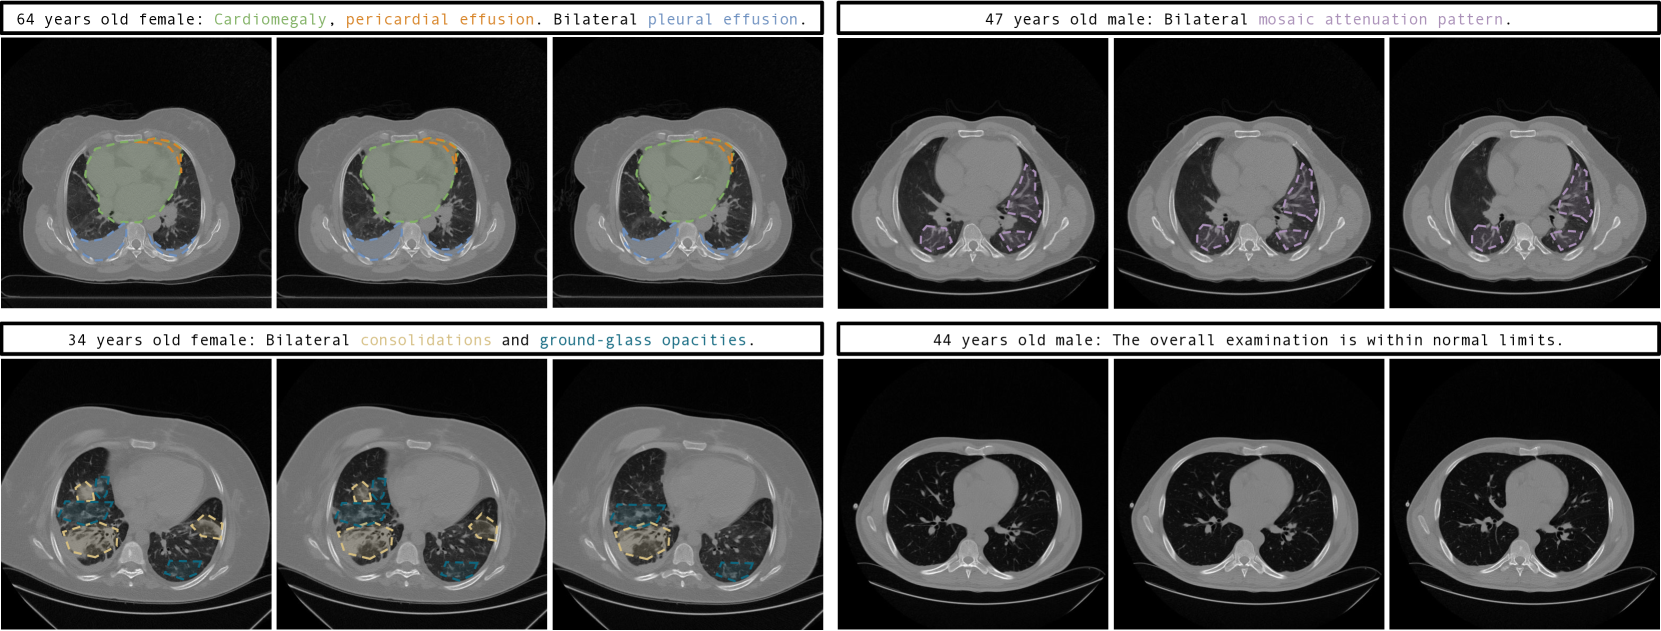

Refer to caption

Figure 4: Three sequential slices from each synthetic 3D chest CT within the practical HU range of [1000HU,+1000HU]1000HU1000HU[-1000~{}\text{HU},+1000~{}\text{HU}][ - 1000 HU , + 1000 HU ] generated based on the given prompt, showcasing GenerateCT’s proficiency in preserving spatial consistency across successive slices. Abnormalities referenced in the prompts are color-highlighted, underscoring our method’s precision in translating textual descriptions into clinically accurate volumetric features.

Qualitative results. GenerateCT effectively translates specific text prompts into 3D chest CT volumes, as shown in Fig. 4. The initial three volumes show distinct pathologies, marked with colored text and areas, consistent across slices, contrasting with a fourth volume of a healthy lung. These volumes display diversity in size, orientation, age, and sex, emphasizing the range of data producible from the text prompts. Fig. 3 further demonstrates GenerateCT’s ability to create comprehensive 3D images by including both sagittal and coronal slices in addition to axial ones. Fig. 5 showcases the model’s cross-attention between text and generated volumes, emphasizing regions corresponding to specific pathologies. This involves averaging attention outputs across heads and relevant tokens corresponding to each pathology in the input prompts, then upscaling the low-dimensional cross-attention outputs to high-resolution CT volume dimensions using an affine transformation. Such visualizations show GenerateCT’s precision in aligning text with the relevant regions, translating medical terms into spatially accurate and clinically significant image features, such as cardiomegaly around the heart, pleural effusion at the effusion site, and consolidation in the affected lung area. We showcase slices from 3D chest CT volumes in the raw HU range of [1000,+1000]10001000[-1000,+1000][ - 1000 , + 1000 ], diverging from standard windowing for more authentic representation. Supplementary material offers varied windowing examples.